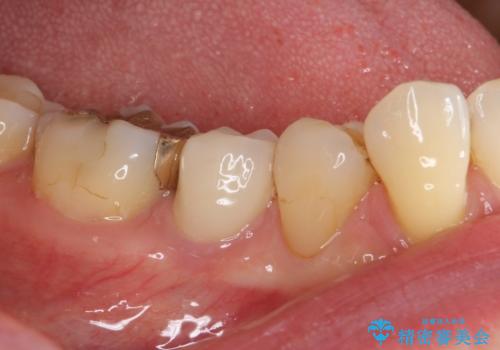

神経が取り除かれた歯であるため、虫歯で歯が失われていく際に痛みを伴わなず、気がついたら大きな穴があいていました。

虫歯を全て除去したうえで新しい土台を築製し、セラミッククラウンにより補綴治療を行うこととしました。

虫歯が歯根深くまで及んでいる場合には歯を部分矯正で引っ張り出したり、歯周外科処置が必要となったりしますが、メインテナンスでレントゲン写真を定期的に撮っていたため、幸いにも矯正や外科処置が必要となる前に補綴治療を行うことができました。